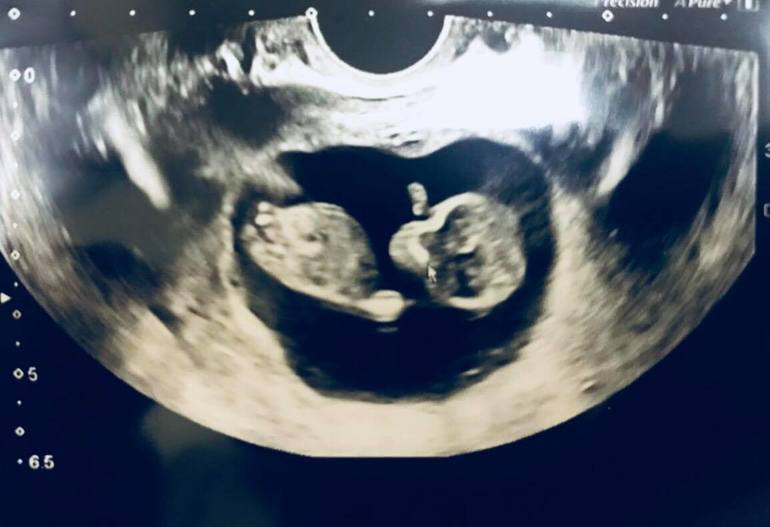

11 недель и 2 дня

Опасения были напрасными, все хорошо, есть небольшой тонус. Но как же я рада была увидеть своего котеночка!))) Совсем большой уже, 4,7 см!))

Крутился, вертелся)) Пальчики на ручках даже видела))

Узист предположил, что это девочка (мы вообще-то мальчика ждем))), но лучше через 3 недельки точно посмотреть.

Ну и фото на память :)